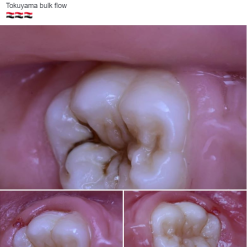

Many patients do not want their teeth to be recognised as new.

They want their characteristic tooth-colour after treatment.

Patients do not always want “brilliant white teeth”.

A touch of colour is sometimes needed to restore your patient’s individual appearance.